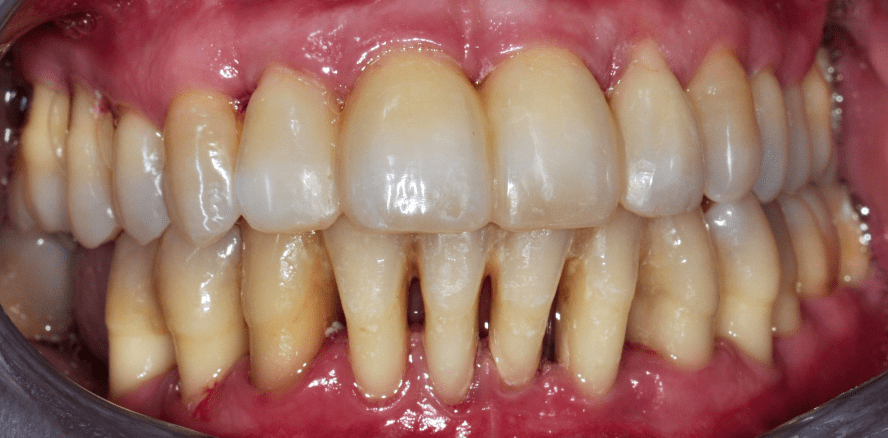

Die Abbildungen 2a–d zeigen die Eingangssituation einer allgemeinmedizinisch gesunden 37-jährigen Nichtraucherin mit Parodontitis Stadium IV Grad C, Falltyp 1 (damalige Diagnose: generalisierte aggressive Parodontitis). Ihr Hauptanliegen war der Zahnerhalt und die Beseitigung der „lockeren“ Zähne. Die Sondierungstiefen lagen generalisiert zwischen 5 und 9 mm. Die AV bei bis zu 12 mm. Die Zähne 33-43 wiesen alle einen Lockerungsgrad III auf. Auch die Oberkieferfront wies einen Lockerungsgrad II auf. Nach der Mundhygienephase erfolgte eine Full-Mouth-Disinfection mit adjuvanter Antibiotikagabe. Die Schienung der Zähne 33-43 erfolgte mittels glasfaserverstärkter Kompositverblockung. Bei Befundevaluation zeigten sich nur noch vereinzelte Taschen von bis zu 5 mm, welche reinstrumentiert wurden. Die Patientin konnte entsprechend in die engmaschige UPT (dreimonatiges Intervall) überführt werden. Zur Verbesserung der Ästhetik und Stabilisierung der gelockerten Oberkieferfrontzähne erfolgte nach Abschluss der aktiven Behandlungsphase ebenfalls eine Verblockung der Oberkieferfrontzähne und Zahnumformung im direkten Verfahren mittels Komposit. Abbildungen 3a–d zeigen die Situation der Patientin zweieinhalb Jahre nach Erstbefundung.